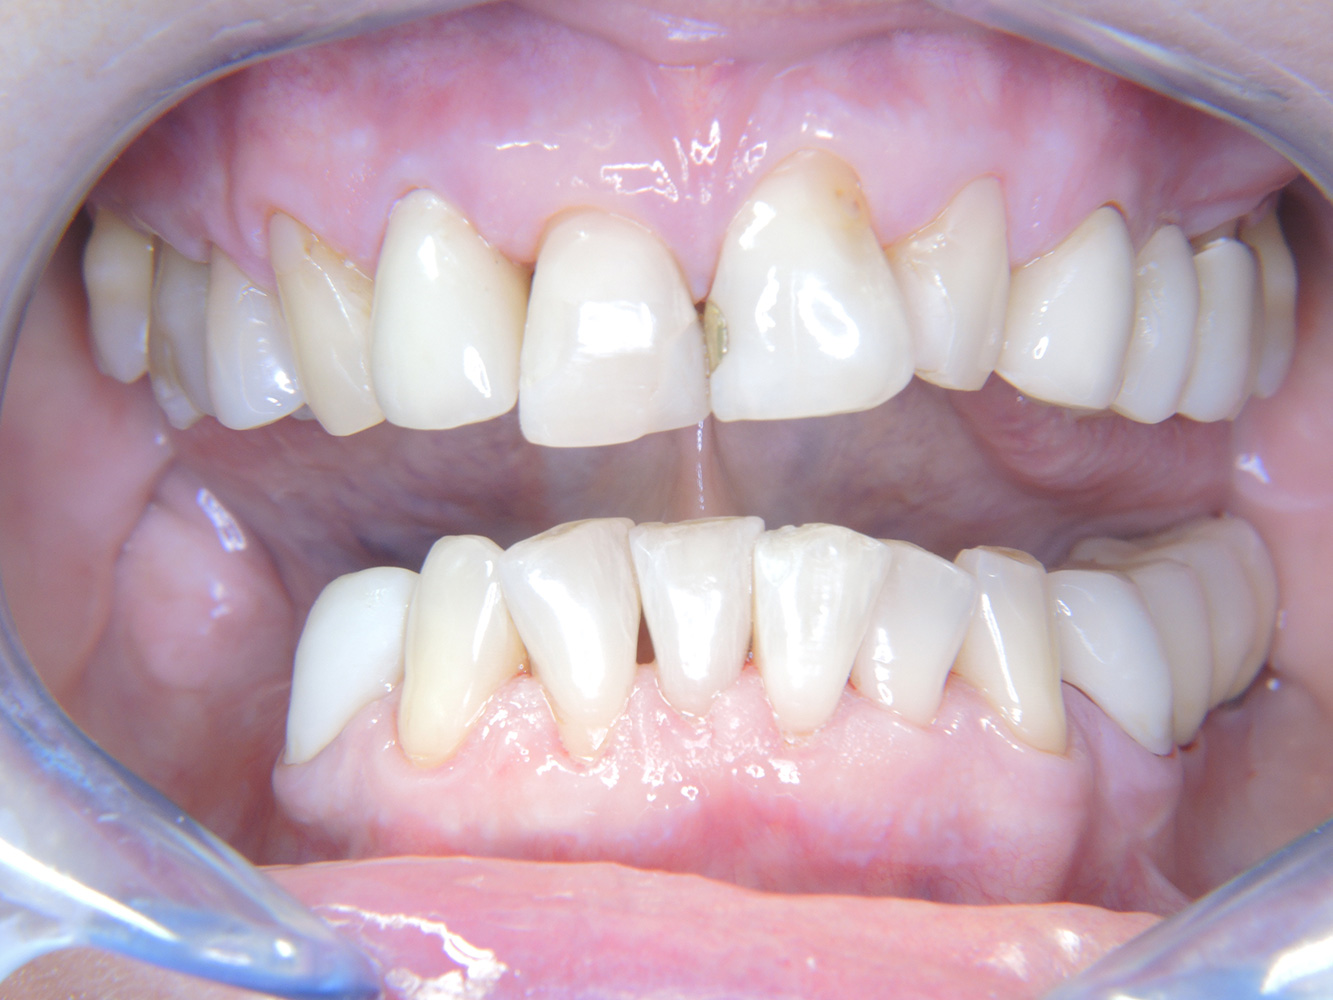

The healthy patient with early periodontal disease*

The 68-year-old patient has no general health conditions and is not taking any medication that may be relevant to her oral health, and her lifestyle does not pose any particular risk. The patient has two dental implants (3rd quadrant, for five years) and a previous case of periodontal disease (stage IV, grade B periodontitis) with tooth loss. Currently the periodontal conditions are stable. However, periodontitis significantly increases the biological complications of implantations and there is a risk of implant loss (21). Four recommendations can be determined for the prophylaxis session.

As the patient does not have any particular risk factors with specific dental implications, the requirements determined from her current state of oral health are crucial. Here, it is recommended that a thorough assessment of periodontal condition be carried out once a year. This will ensure that any potential progression of the previous periodontal disease or development of peri-implantitis can be responded to in good time.

Despite the stable conditions, it is also crucial for the instructive/motivational discussion to be conducted with this patient. Particular attention should be paid to teaching the patient how to care for the implants correctly. Here in particular, good at-home maintenance can have a significant impact on the long-term stability of oral and implant health.

In terms of instruments, specific procedures are required for use with implants. In order to preserve the surface of the implant while cleaning it effectively, it is essential to choose suitable powders and instruments such as the targeted use of air polishing devices with special periodontal tips. Which powder is most suitable can be determined according to the needs and risk. For example, in addition to the appropriate degree of abrasion, dietary requirements (including sugar-free, low-salt) may also be taken into account.

Because the patient has implants and a history of periodontal disease, she is at risk of developing peri-implantitis. It is therefore recommended that she attend a recall session every three to four months.